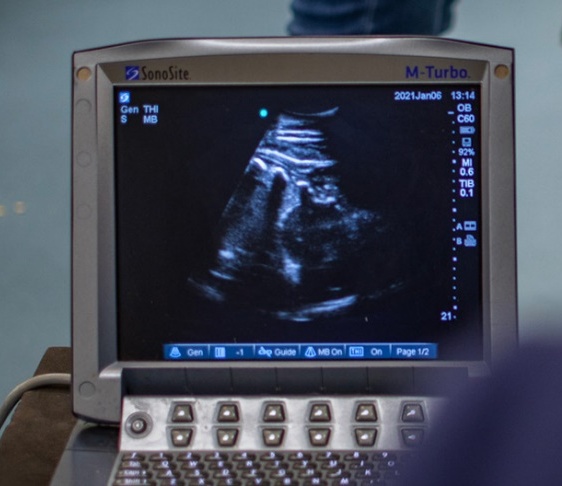

Pre-breeding checks are routine ultrasound scans of the uterus, ovaries, and other examinations to determine the optimal time to breed. This evaluation normally includes ultrasound scans, vaginal evaluation, and all the follow-ups in order to ensure the most accuracy of breeding. Each mare is treated to suit her needs and/or difficulties according to each animal's individuality.

The recipient mare will be checked between 12 to 14 days (embryo age) to determine confirmation. Follow-up will be done at 30 days of pregnancy to ensure the embryo has a heartbeat and viability confirmation. Follow-ups on these mares are necessary every couple of weeks until 2 months, which is the critical period.

We will be assisting and consulting farms throughout the season with close follow-ups on these facilities. The service will be monitored throughout the entire pregnancy period to decrease the chances of losses during pregnancy, plus all consulting during the pregnancy period to ensure the best results and full-term pregnancy.